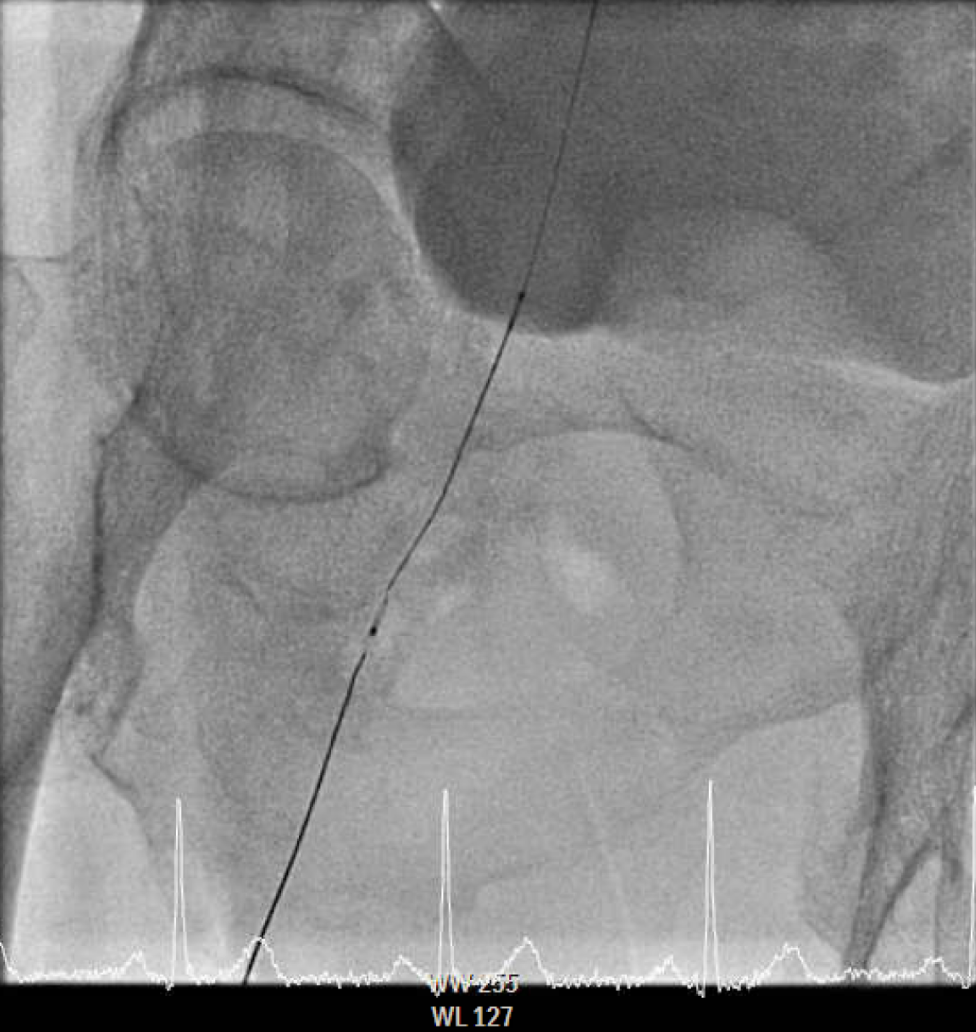

The procedure utilized a hybrid retrograde and antegrade approach. Retrograde access was established via a micropuncture kit under angiography guidance into the distal Superficial Femoral Artery (dSFA), but wiring attempts failed due to an intervening aneurysm, necessitating a switch to the antegrade route from the left brachial artery. A wire escalation technique, assisted by a microcatheter, successfully crossed the extensive CTO, and was met with retrograde microcatheter and externalized via the dSFA puncture site (retrograde access), establishing through-and-through wire access. Following initial balloon predilation and IVUS confirmation of diffuse thrombus, extensive angioplasty was performed. Definitive treatment involved deploying multiple overlapping GORE¢ç VIABAHN¢ç Endoprosthesis diameters (from 6mm to 8mm) from the dSFA proximally to the pEIA via left femoral access, effectively treating the long occlusion and excluding the aneurysm. A COOK Zilver Flex iliac stent reinforced the proximal landing zone. The stented segment was rigorously post-dilated up to 12 atm. The procedure concluded with a Drug-Eluting Balloon (DEB) PTA (BOSTON Ranger Paclitaxel-Coated PTA Balloon Catheter) to the dSFA to mitigate restenosis in the non-stented region. Final angiography confirmed good flow without distal embolization.